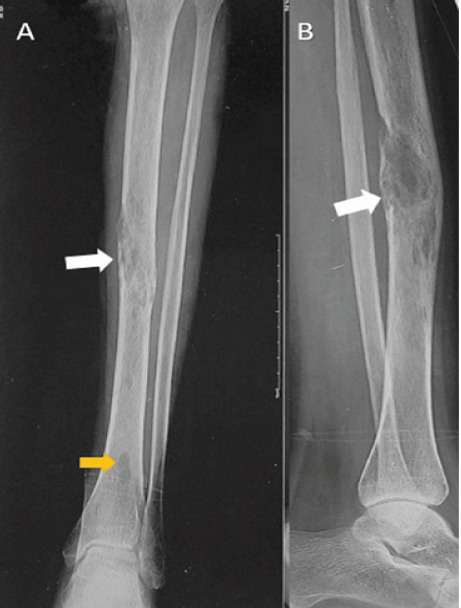

Case report: We present one such case of a young female who presented with chronic pain in the leg for 2 years and difficulty in walking. The clinical and radiological evaluation, including computed tomography angiography, confirmed the diagnosis of intraosseous venous malformation of the tibia. The lesion was managed initially by sclerotherapy and endovenous laser ablation by the intervention radiologist; however, the bony lesion required prophylactic intramedullary nailing in view of persistent pain affecting her daily activities.